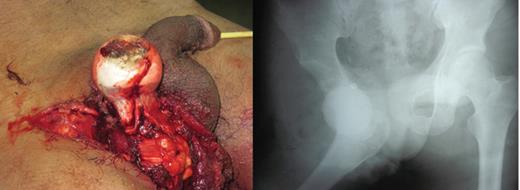

A 23-year-old male pavement dweller was brought to the emergency department of this hospital after being hit by a tempo. The patient was in a state of shock with an open right-sided anterior hip dislocation with the femoral head being visible in the inguinal region (Fig. 1). The neurovascular status of the right lower limb was intact. Immediate resuscitation was done and hip radiographs (Fig. 1) were taken, which showed an anterior-inferior dislocation with an inferior pubic ramus fracture on the left side. The patient was immediately transferred to the operating room where the wound was thoroughly debrided and the femoral head was relocated within 5 hours of sustaining the trauma (Fig. 2). The wound after surgical debridement was 8 × 6 cm in dimensions, which was primarily closed after checking for the stability of the reduction. The patient was started on intravenous metronidazole, amikacin and ceftriaxone for 5 days, followed by oral amoxicillin for a week. The patient was kept non-weight-bearing on skin traction for 6 weeks. The wound healed satisfactorily with no evidence of infection, nor any episode of re-dislocation at 6 months (Fig. 3). The patient was unfortunately lost to follow-up.

Figure and radiograph showing an open anterior hip dislocation.